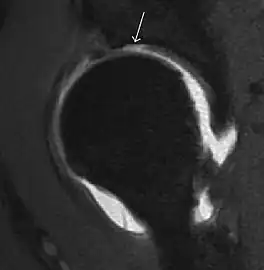

Synovial chondromatosis can be confidently diagnosed by X-ray when calcified cartilaginous chondromas are seen. However, other synovial proliferative processes, such as pigmented villonodular synovitis, require MRI for accurate diagnosis, although noncalcified synovitis can be suspected in radiographs by indirect signs, such as soft tissue swelling and/or erosions in the femoral head, femoral neck, or acetabulum (Figure 7).[1]

Figure 7:

Axial CT image of pigmented villonodular synovitis eroding the posterior cortex of the femoral neck.[1]

Sagittal T2* gradient echo image showing a posterior soft tissue mass with hypointense areas secondary to hemosiderin deposition.[1]

X-ray of synovial chondromatosis.[1]

CT of synovial chondromatosis.[1]

In synovial proliferative disorders, MRI demonstrates synovial hypertrophy. In the case of PVNS, characteristic foci of low signal intensity related to hemosiderin deposition are better seen on gradient echo T2* images (Figure 7). In the case of synovial osteochondromatosis, the synovial hypertrophy is accompanied by intermediate signal cartilaginous loose bodies and/or low signal calcified loose bodies.[1]